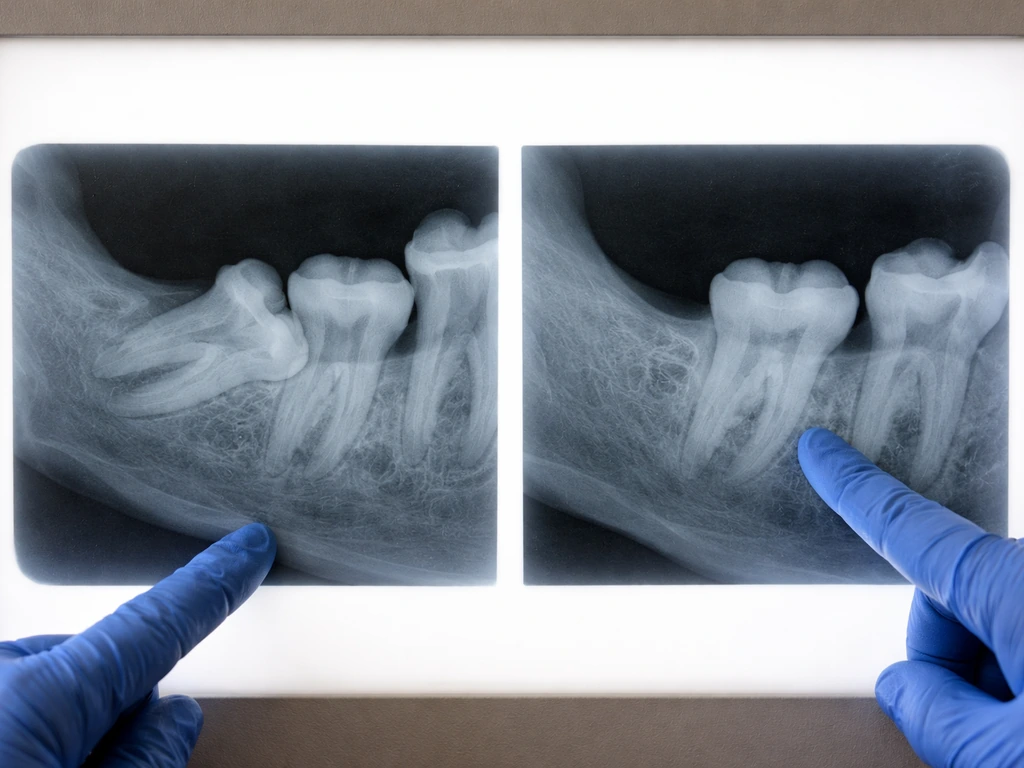

A standard dental X-ray (periapical or panoramic) is usually the first step. A panoramic radiograph gives your dentist a broad view of all the teeth, the jawbone, and any remaining root tips or bony structures. It is good for a general assessment of what is going on in the wisdom tooth area. However, panoramic X-rays have limits, especially for deeply impacted or complex cases.

For more detailed evaluation, a CBCT scan (cone beam computed tomography) is the gold standard. The American Association of Oral and Maxillofacial Surgeons recommends CBCT in selected cases because it provides three-dimensional imaging of the tooth, roots, surrounding bone, and nearby nerve structures in much greater detail than a flat panoramic image. If there is any uncertainty about retained root tips, residual tissue, or an impacted tooth that was never removed, a CBCT scan will give your oral surgeon a clear, precise picture.

The imaging will not show a regenerated tooth, because there is no such thing to show. What it can reveal is a retained fragment, a previously undetected impacted molar, a supernumerary tooth, or bone and gum changes that explain your symptoms. That clarity is exactly what you need to make a treatment decision.